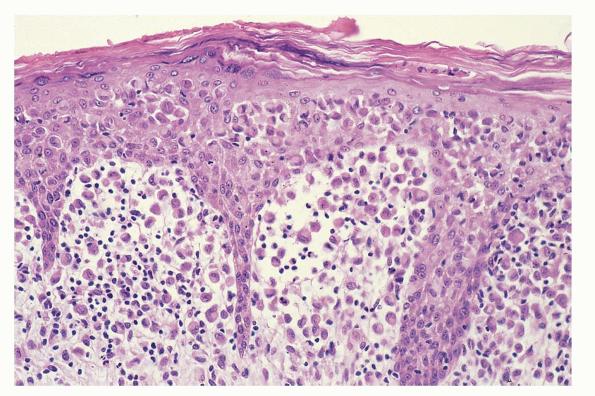

Langerhans cell histiocytosis = كثرة الخلايا الناسجة لانغرهانس

OLYMPUS DIGITAL CAMERA